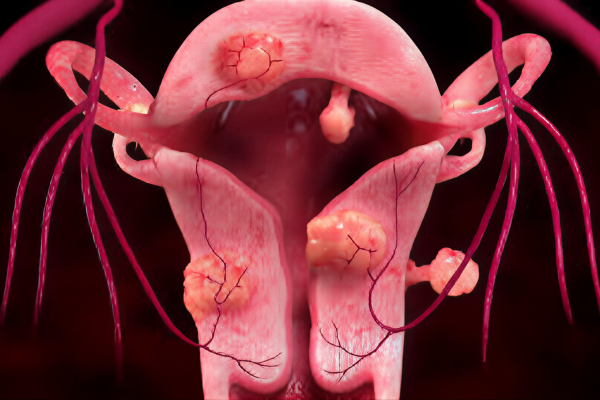

Uterine fibroids and postpartum hemorrhage cause heavy bleeding, pain, and anemia. Surgery may not always be preferred or possible.

Uterine artery embolization blocks blood supply to fibroids or bleeding vessels, controls hemorrhage, shrinks fibroids, and preserves the uterus.